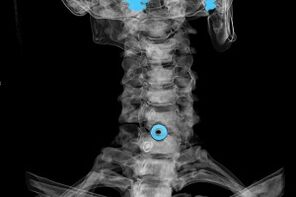

The diagnosis is established on the basis of characteristic symptoms, and the following are used:

- x-rays.The method is ineffective, especially in the last stages of the development of osteochondrosis.

- MRI (magnetic resonance imaging) of the cervical spine.A method that allows you to see the bone structures, the disc herniation, their size and direction of development.

- Computed tomography.It is a less effective solution than MRI, as the presence and size of hernias are difficult to determine.